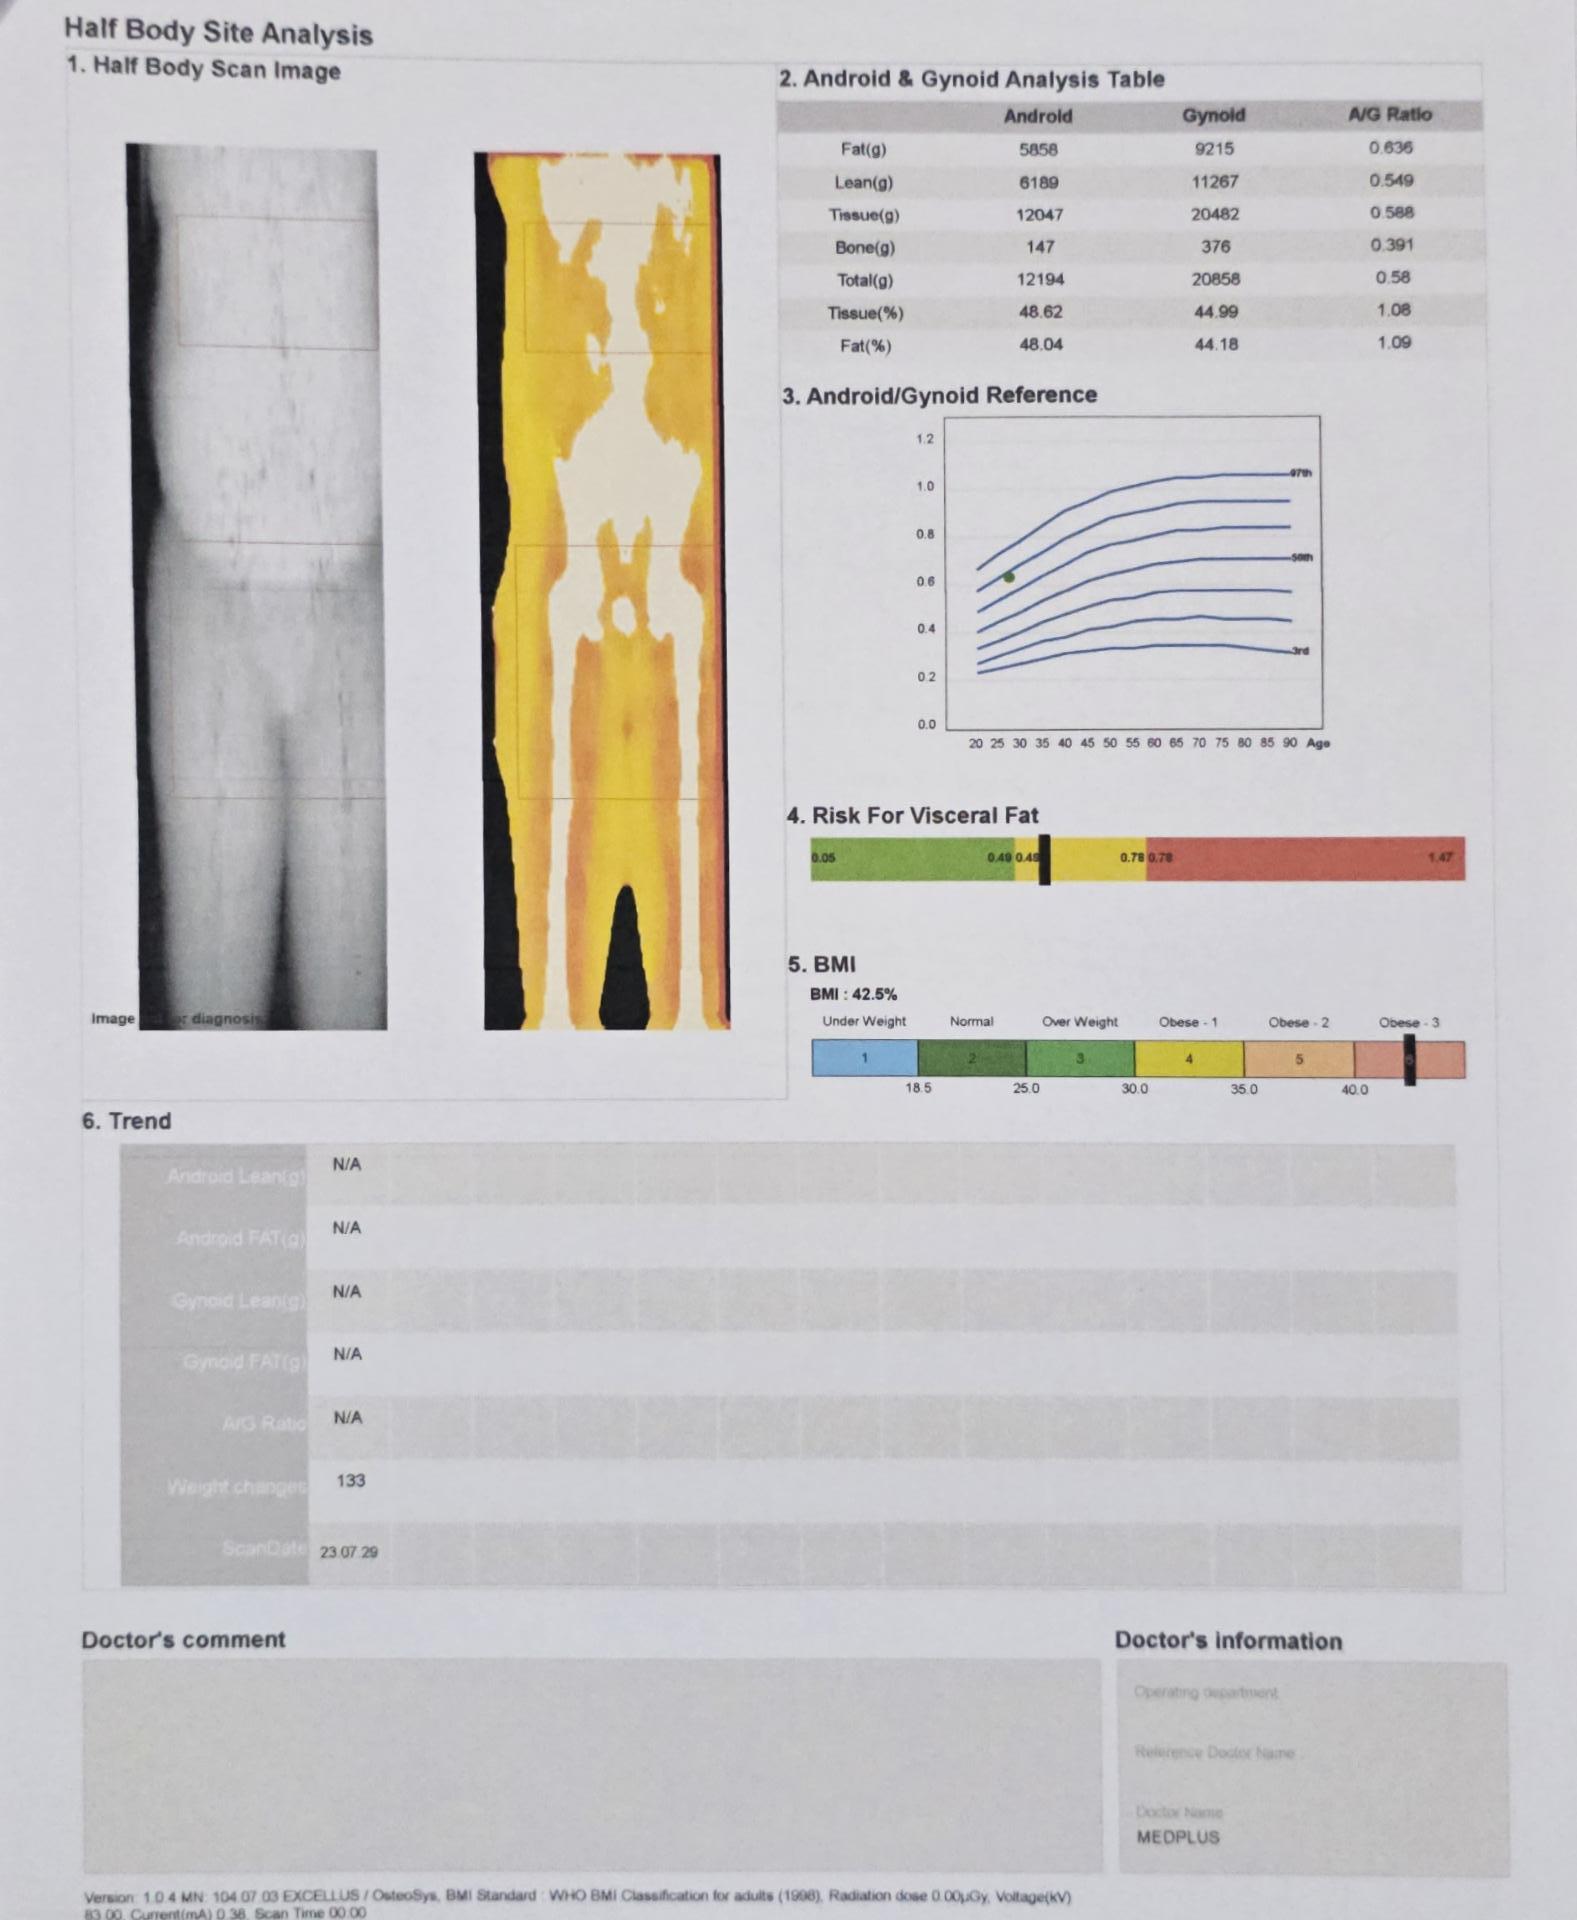

My Body Fat Percentage is 48. Method Dexa Scan r/Fitness_India Body Fat Percentage Dexa Scan A dexa scan provides a clearer understanding of your body composition and skeletal health. A dexa scan are a highly accurate way of estimating body fat percentage. Map and pinpoint your precise muscle gains and fat. A dexa scan was originally used in healthcare setting to assess bone health, however, they also provide the most accurate. The main numbers of. Body Fat Percentage Dexa Scan.